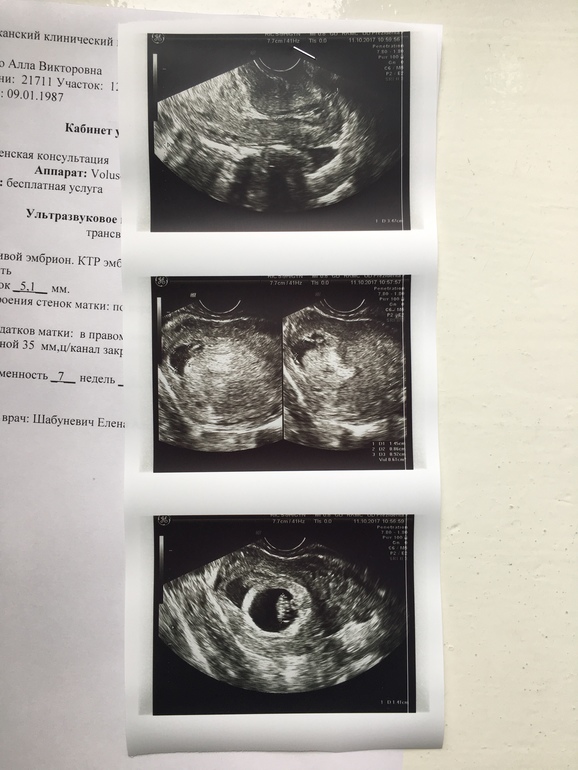

Вообщем, сходила на контроль УЗИ. Эмбриончик мой растёт, сердцебиение есть, но угроза не ушла никуда. Вроде так уже не тянет живот, выделений нет тьфу тьфу тьфу. Терапию врач ту же сохранила:дюф, магне в6, фолиевая. Предлагали стационар, но написала пока отказ. Муж не справится с малым сказал... вот и как дома сохраняться с маленьким ребёнком?!.. было ли у кого так же ? Долго ли угроза была? Вот УЗИ мое

так и у вас отслойка: ПЯ должно быть плотно к матке, а у вас "черное пятно"- это место отслойки пя от стенки матки, лопнули сосуды,потекла кровь и скопилась между пя и маткой, т.е. на месте "черного пятна" пя к стенке не прилеплено. Как смогла объяснила. У вас гематома пока не большая и она не длинная, судя по узи, вот если она будеть опоясывать пя, то это уже серьезная отслойка.